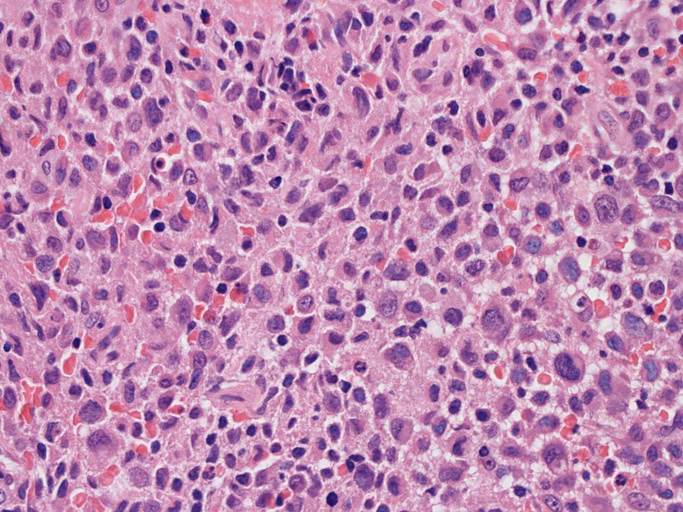

Langerhans cell sarcoma

LCSの病理組織所見

Langerhans cell histiocytosisの高悪性度 variantで明らかな悪性像を示すLangerhans cellの腫瘍性増殖と定義される(WHO, 2008)

大型細胞の増殖よりなる腫瘍。縦溝,しわ,切れ込みのある核をもった大型細胞も出現する。クロマチンは顆粒状で核小体も明瞭である。核分裂は >50/10hpfと多い。eosinophilsは少ない。壊死が多発することがある。未分化ないし低分化な細胞像, 組織所見のため鑑別診断は多岐にわたり、的確な免疫染色を行う必要がある。

皮膚に異型細胞の浸潤がみられる。異型細胞は表皮内に浸潤するほか、表皮真皮境界部, 真皮, 皮下脂肪組織にもびまん, 結節様の浸潤所見を示す。血管周囲に浸潤、集蔟する所見も多く見られる。 増殖浸潤細胞の核には類円形や腎臓形, またはへこみ, 切れ込み, 溝などを有する多型な核が認められる。クロマチンは粗でvesicularな核が多い。核小体の明らかな核もある。好エオジン性の核内封入体様構造も少数に見られた。mitosisは容易に認められる。hyperchromaticな多型核, bizzarreな細胞が高頻度に認められ異型度は高いと考えられる。細胞質は境界不明瞭, 淡明または泡沫様の 好エオジン性胞体である。

免疫染色 浸潤細胞はCD1a+, S100+, Langerin+, HLA-DR+, CD4+, CD45+, CD68+. MIB-1 index:24.4%

Speaker's Pathological Diagnosis: Langerhans cell sarcoma, skin, rt. knee, biopsy